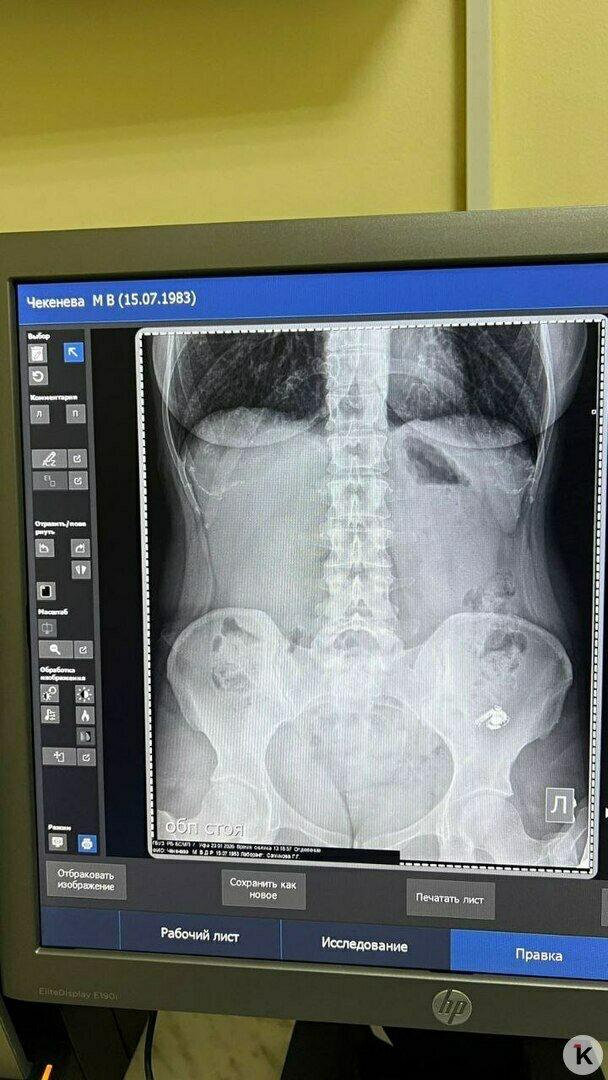

Мария очень испугалась: было непонятно, как поведёт себя внутри организма электронный прибор. Но в травмпункте девушке сделали снимок и обнаружили наушник в желудке.